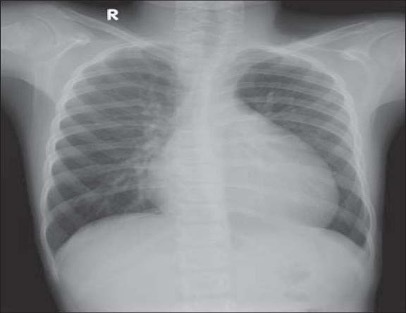

What features are seen on this CXR? What is the likely diagnosis?

Bilateral airway shadowing

Pulmonary oedema